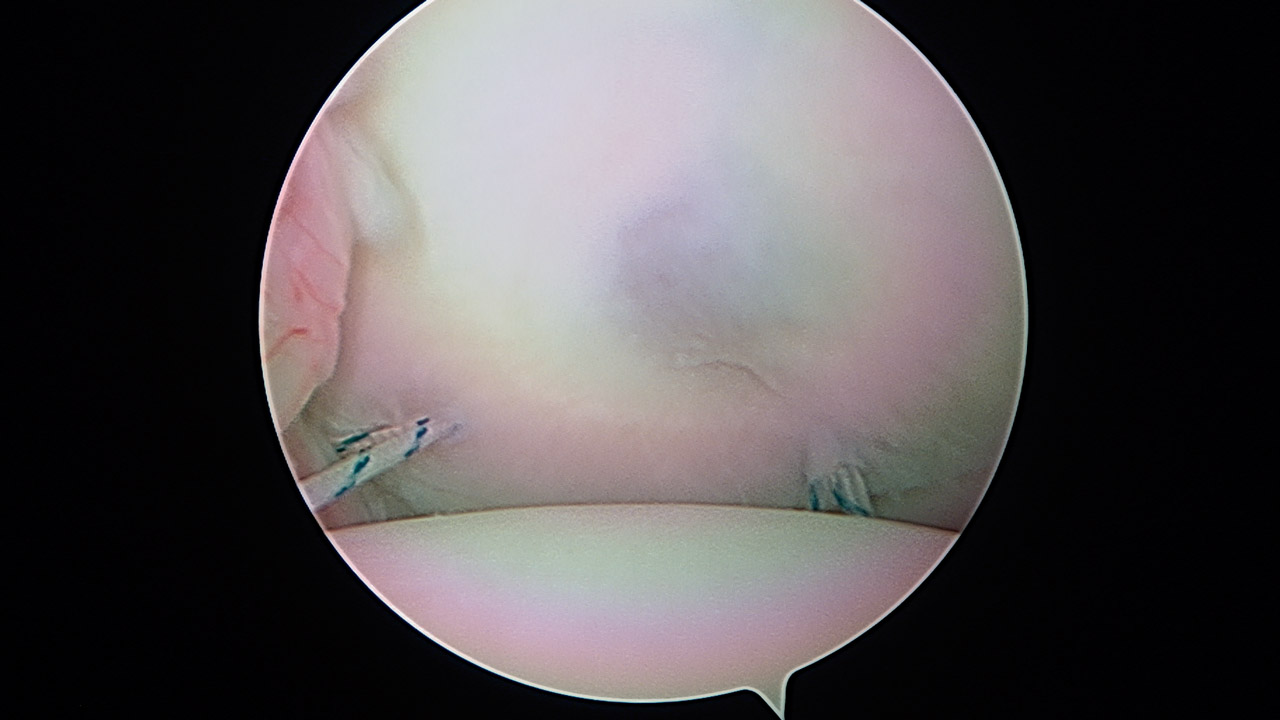

Paso 1: plicatura inferior

Una vez intraarticular, se explora el labrum y los ligamentos, con un gran receso inferior. Realizamos una plicatura con un anclaje Iconix® 1,4 (Stryker, Kalamazoo, Mi) posteroinferior que se deja sin anudar y otro anclaje Iconix® 1,4 anteroinferior exactamente igual y simétrico. Con este gesto, se pretende retensar el LGHI, tanto anterior como posteriormente, los cuales se anudarán al terminar la ligamentoplastia (Figura 4).